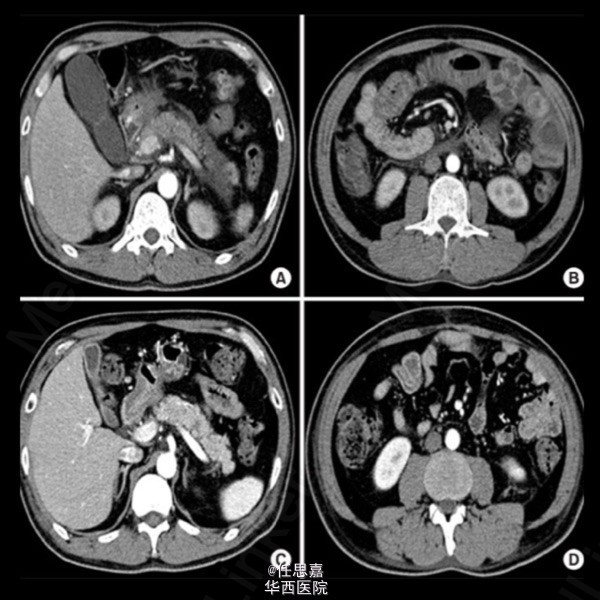

53岁男性,因“腹部绞痛伴胆汁性呕吐3天”入院,入院前10天患者出现双踝关节疼痛、肿胀,双上下肢远端皮疹。无外伤史,无药物史,勿暴饮暴食,近期无饮酒史,既往体健,无家族史。查体:T 36.4℃,BP 130/80mmHg,HR 70次/分,双上下肢远端可见红斑,双踝关节肿胀伴轻压痛。全腹压痛,中上腹为主,无明显反跳痛,无肝脾大,肠鸣减少,胫前水肿。辅助检查:HGB 142g/L,WBC 16.2*10^9/L,PLT 493*10^9/L,CRP 5.74 mg/dL,GLU 136 mg/dL, BUN 26 mg/dL, CREA 1.4 mg/dL,血Ca 8.0 mg/dL,血清白蛋白 18g/L,AMY 3,093 U/L,LIP 4,063 U/L, ALT 103 IU/L,AST 128 IU/L,小便隐血(+),24h尿蛋白定量4.9g,血清IgA 331 mg/dL。RF(-),ANA(-),ANCA(-)。腹部CT显示:胰周积液,多节段肠壁增厚。肾活。检:毛细血管增生性肾小球肾炎,免疫荧光法可见肾小球系膜IgA沉积。皮肤活检:非特异性血管周围少量淋巴细胞浸润。考虑诊断“过敏性紫癜并发急性胰腺炎,肾小球肾炎”。予胃肠减压,甲强龙静滴60mg/d,8天后患者AMY、LIP恢复正常,第9天复查腹部CT未见明显异常。随访3月,小便仍有隐血、蛋白。 摘自J Rheum Dis. 2012 Feb;19(1):43-46. English. Published online February 28, 2012. http://dx.doi.org/10.4078/jrd.2012.19.1.43